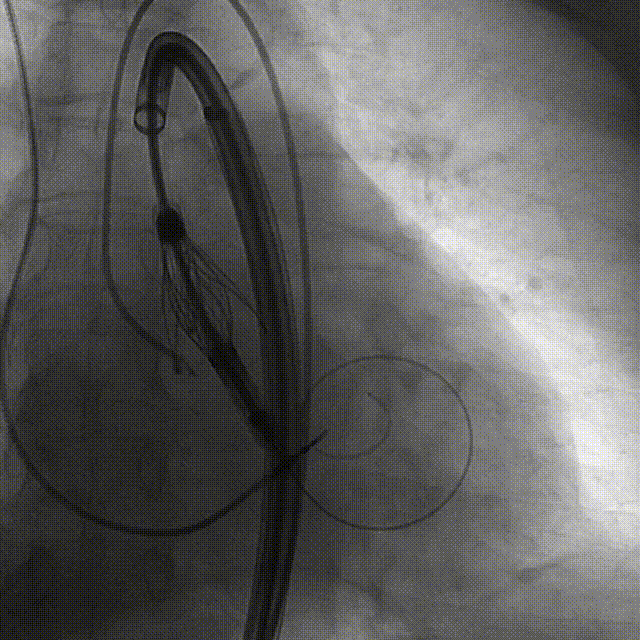

手术过程:5A 标准化流程SOP

术前右窦中心造影

大鞘植入

瓣膜调弯解离

定位键窦对齐验证

定位键入窦验证

深度检查

一键释放

后扩后造影